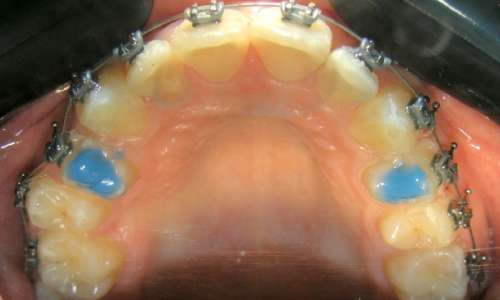

Передние накладки (bite turbos) – используются при низкой высоте прикуса, глубоком резцовом перекрытии, заднем положении нижней челюсти.

Боковые накладки (bite blocks) – для разобщения прикуса и комфортного скольжения нижней челюсти